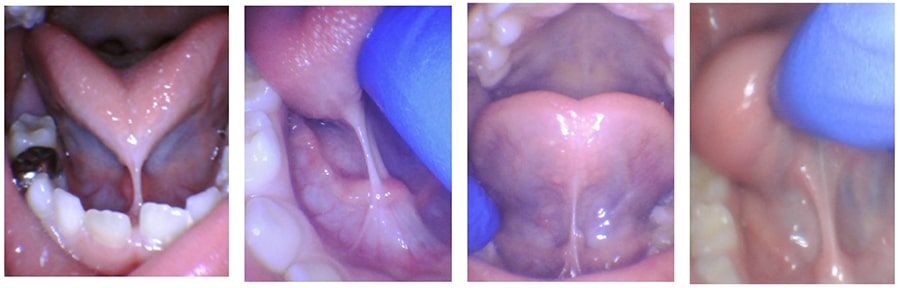

Variable Appearance

Appearance

Children’s tongue-ties can appear very tight or mildly tight. The symptoms and function are much more important than appearance.

All of these strings under the tongue were causing problems, even ones that don’t appear as significant.